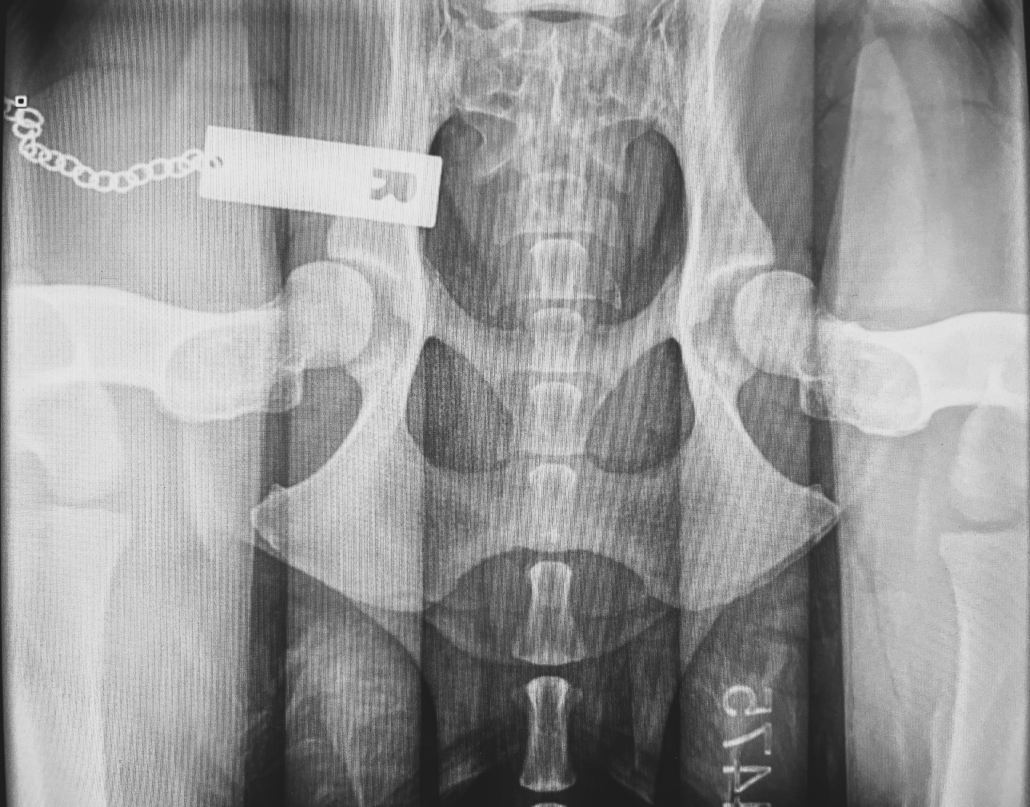

The Hip Extended view, on its own, has poor predictive accuracy for diagnosis of Hip Dysplasia, unless there is radiographic evidence seen (femoral periarticular osteophyte formation, subchondral sclerosis of the craniodorsal acetabulum, osteophytes and joint remodelling). This view actually forces the femoral heads into the acetabulum, therefore masking joint laxity.

- Three (3) radiographs will be taken – a hip extended view, a compressed and distracted view.